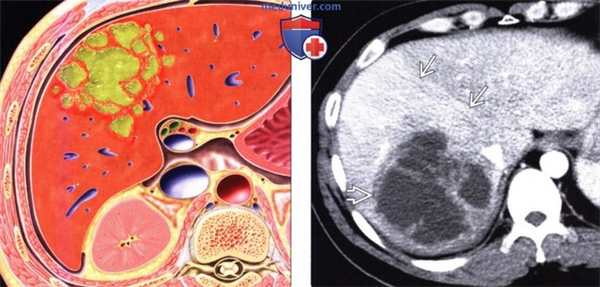

(Слева) На рисунке показаны периферические многокамерные скопления гноя с воспалительными изменениями окружающей паренхимы печени.

(Справа) На аксиальной КТ с контрастным усилением у женщины 33 лет визуализируется образование сложной структуры с множественными септами (абсцесс печени). Обратите внимание на четкую демаркационную линию, отделяющую абсцесс от паренхимы правой доли печени, накопившей контраст; участок преходящего различия плотности печени, обусловленный гиперемией стенки абсцесса. У пациентки также была выявлена окклюзия задней правой ветви воротной вены (не продемонстрирована), обусловленная тромбофлебитом.